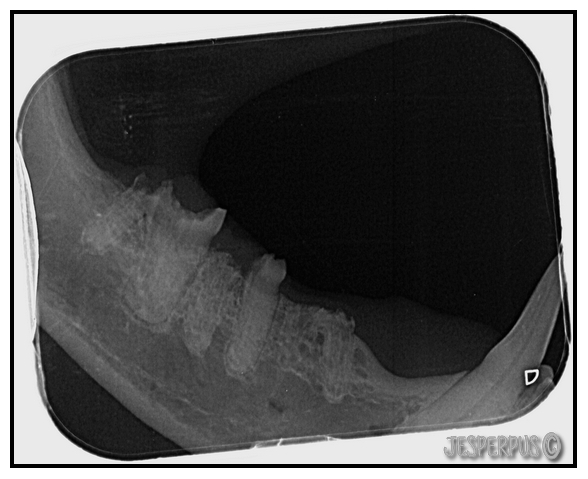

Men for å være helt sikkert, ble det tatt røntgen av alle tennene mine:

Se og røntgenbilder av katt med alvorlig TR under, tennene er nesten helt smuldret bort!